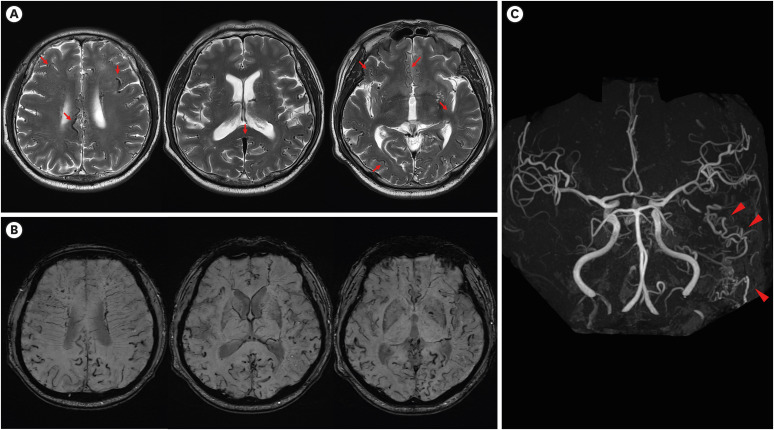

The Multifocal Dural Arteriovenous Fistula Presumed to Present as a Progressive Cognitive Impairment.

假定为进行性认知障碍的多灶硬脑膜动静脉瘘。